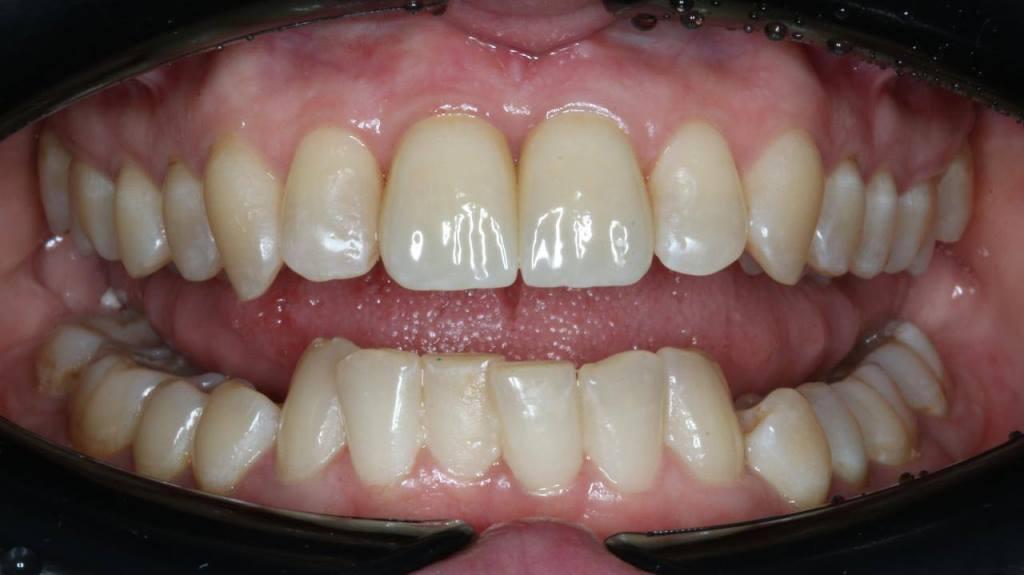

Зубо-альвеолярная реконструкция подразумевает немедленное протезирование. Необходимо во время операции получить достаточную стабильность имплантатов, чтобы ортопед смог сразу изготовить временные коронки, которые будут поддерживать контур мягких тканей. Пациент уходит из клиники с зубами.

Фото 8, 9, 10.

И через полгода после интеграции происходит замена временных коронок постоянными. Довольны результатом и врачи и пациентка!

Фото 11, 12, 13, 14.